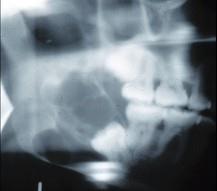

问题 女,32岁,右下后牙龈向外膨隆,后牙渐松动3个月。X线片(如图)示右下颌磨牙区颌骨呈蜂房样改变,病变区牙根呈锯齿状吸收。该病人最可能的诊断是()

选项 A.右下颌骨角化囊肿 B.右下颌骨骨巨细胞瘤 C.右下颌骨骨肉瘤 D.右下颌骨成釉细胞瘤 E.右下颌骨中央性颌骨癌

答案 D